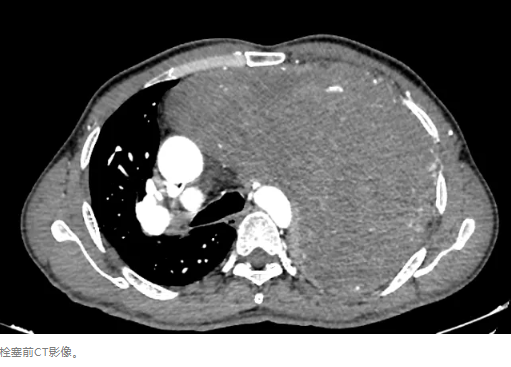

4、最后也是最重要的,于2024年9月14日在介入科主导下行肿瘤相关滋养血管栓塞治疗,治疗后复查胸部增强CT对比,见肿瘤血运明显减少。